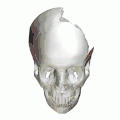

Animation. Left parietal bone removed. Squamosal sutures shown in red. -